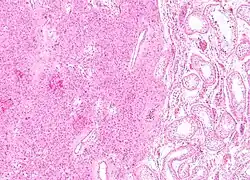

| Micrograph of a granulosa cell tumour, a type of sex-cord–gonadal stromal tumour. H&E stain. | |

Definitive diagnosis of these tumours is based on the histology of tissue obtained in a biopsy or surgical resection. In a retrospective study of 72 cases in children and adolescents, the histology was important to prognosis.[8]